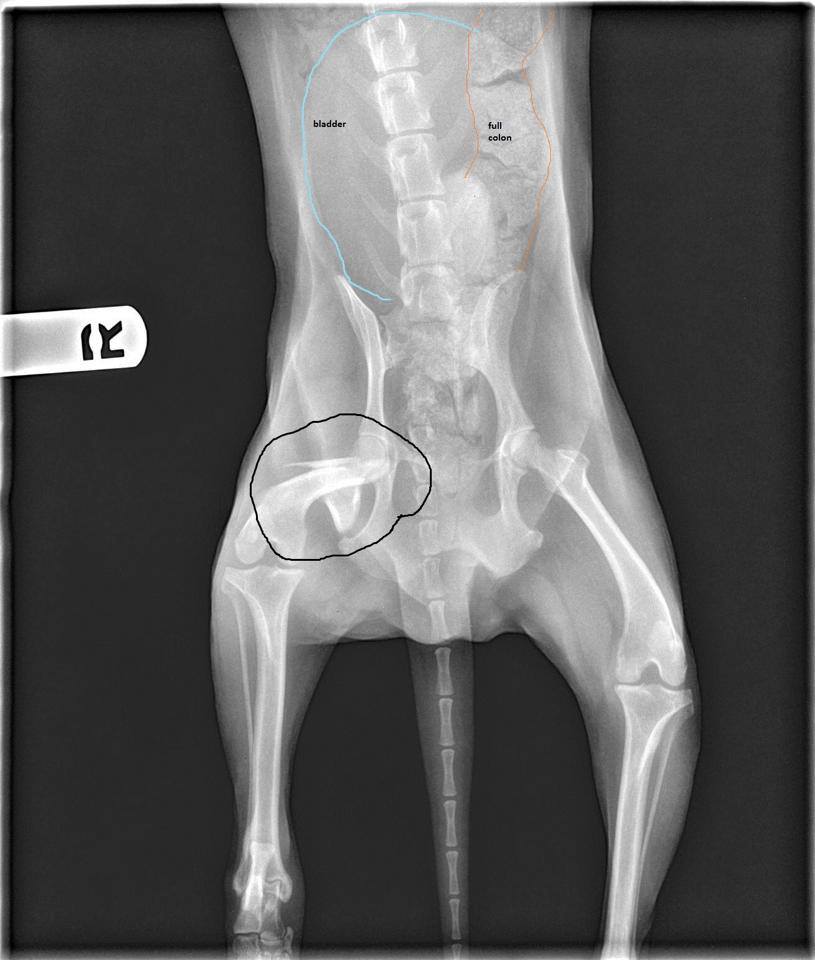

Cotton Xray 2 M.A.I.N. Medical Animals In Need, Dog Rescue in Does Cotton Show Up On Xray cotton balls wouldn’t show up, but cotton balls usually aren’t going near you during a surgery. Wounds with a foreign body sensation should be evaluated. This missing item is a surgical. Clinically, retained sponges may be asymptomatic or result in a granulomatous response with abscess development, intestinal obstruction, or fistula formation. if a surgical instrument is left inside. Does Cotton Show Up On Xray.